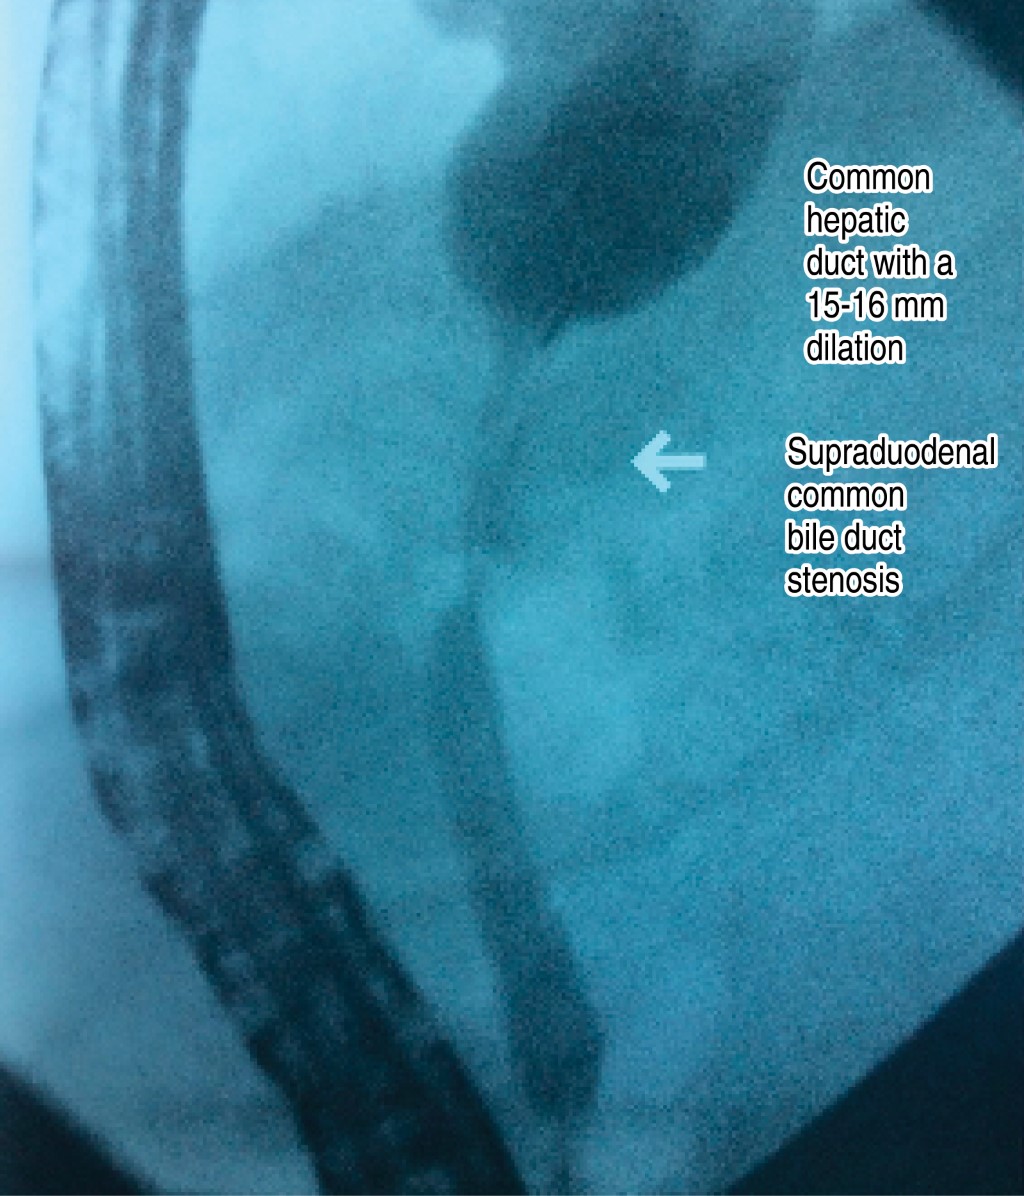

Due to the CT scan findings, it was decided to perform an endoscopic retrograde cholangiopancreatography (ERCP), which reported the following (Figure 3): "small ampulla of Vater, with ectropion of the ampulla, null biliary drainage. Intrahepatic biliary tract with severe dilatation. Extrahepatic bile ducts with dilatation of the common hepatic duct between 15-16 mm, pencil point narrowing zone at the level of the supraduodenal portion of approximately 2 cm in length, null biliary drainage. Selective sphincterotomy of the biliary tract was performed, obtaining abundant purulent material and cellular detritus. An endoprosthesis is placed. Conclusion: intrahepatic bile duct dilatation, Klatskin tumor type IV, cholangitis".

Figure 3